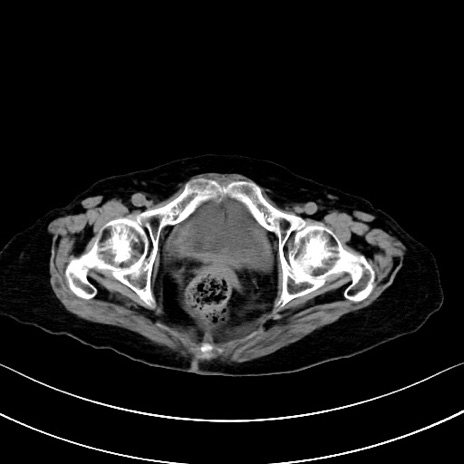

症例40(横断像)他院1日前

横断像